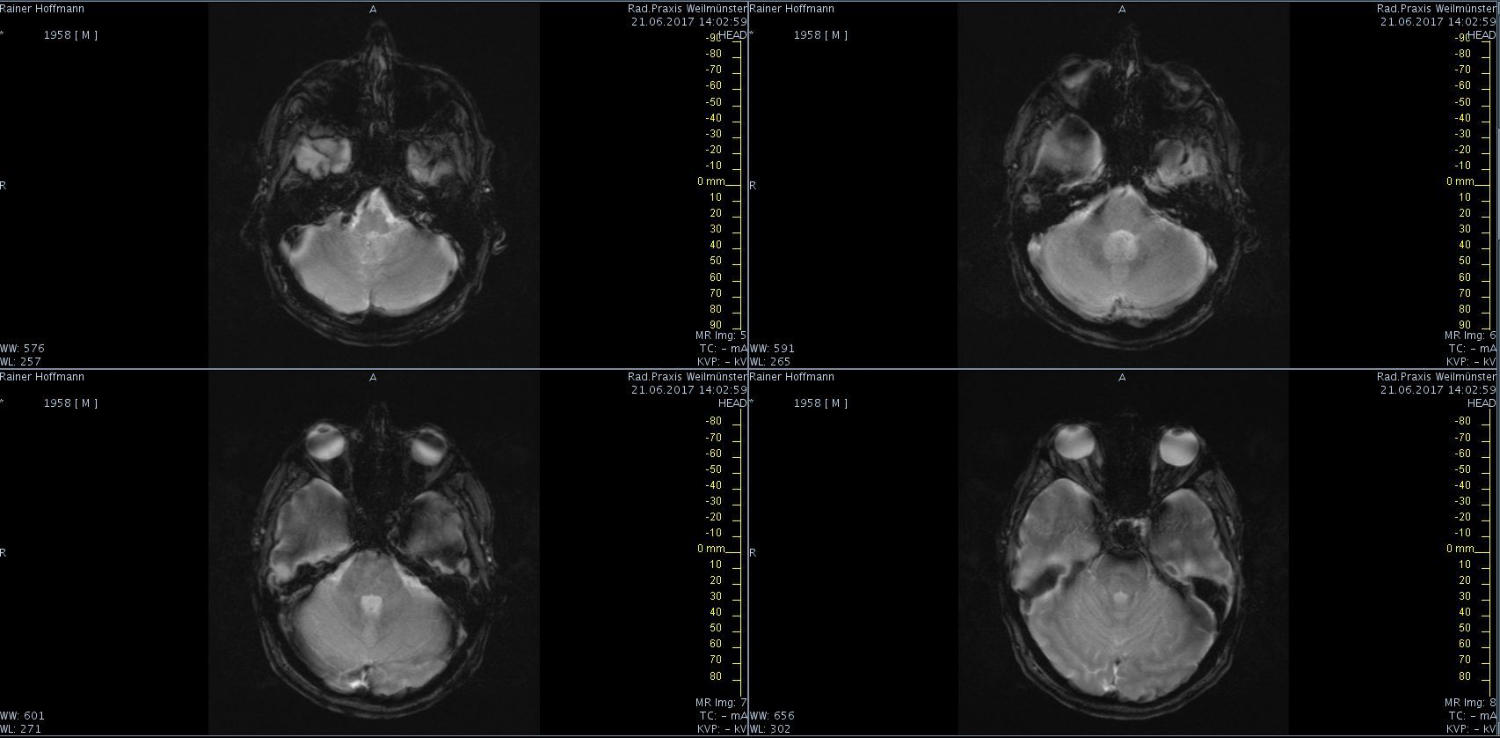

Das ist ja ganz toll, dass Ihr die Seite so schnell gefunden habt. Ich zeige euch jetzt ein ganz, ganz anderes Paßfoto von mir. Es könnte Ähnlichkeiten zu anderen lebenden oder bereits verstorbenen Personen geben. Wenn Ihr das erste Bild oben links anklickt wird es ver- größert dargestellt. Dann kann man mit den Pfeiltasten am unteren Bild- rand durch meinen Kopf blättern. Es gibt nicht viel zu sehen. Vielen Dank an Martina für Ihre Hilfe.

MRT